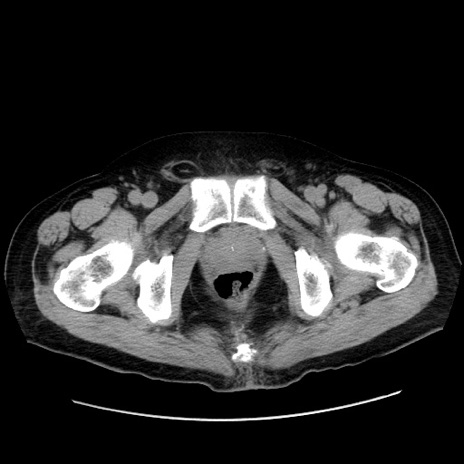

症例30(横断像)

【症例】80歳代男性

【現病歴】約6時間前から臍下部痛が出現。次第に腹部膨隆・背部痛も生じてきたため来院。背部痛の場所は変化しない。

【身体所見】意識清明、BT 36.3℃、BP  131/87mmHg、P 87bpm、SpO2 100%(RA)、臍周囲自発痛・圧痛あり、反跳痛なし、自発痛部位に一致して板状硬あり、腹部膨隆、腸雑音減弱、CVA tenderness両側陰性。

【データ】WBC 19600、CRP 0.33